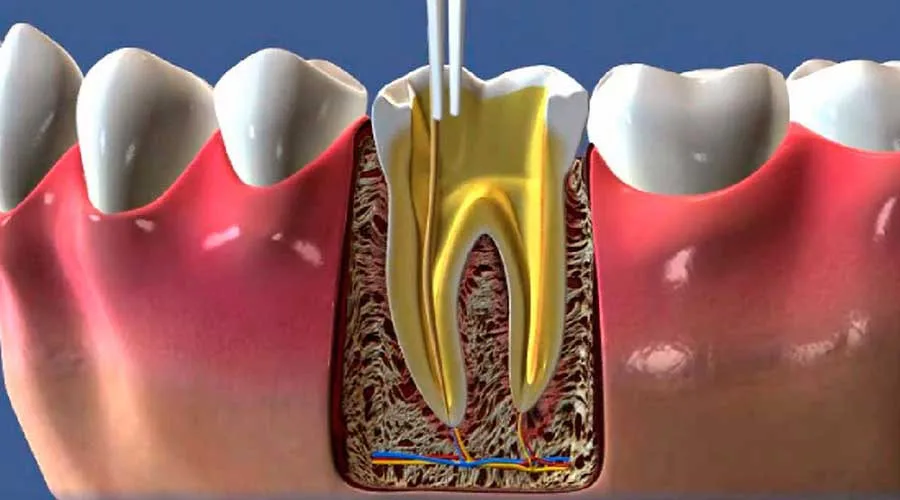

Etapas do Procedimento

Após o diagnóstico, o procedimento é realizado em etapas.

Primeiramente, o dentista anestesia a área afetada.

Em seguida, ele remove a polpa danificada, limpa e desinfeta o canal radicular.

Por fim, o canal é preenchido com materiais biocompatíveis.